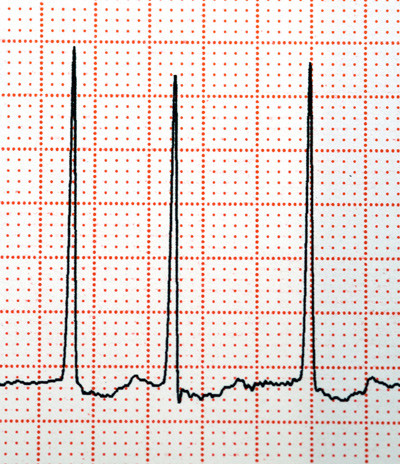

Illustrasjonsfoto: Science photo/NTB scanpix